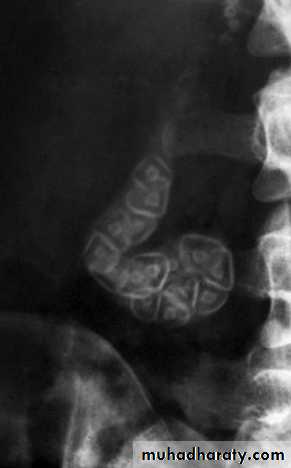

RADIOLOGICAL INVESTIGATION OF THEBILIARY TRACTPlain radiographA plain radiograph of the gall bladder will show radio-opaquegallstones in 10% of patients with gallstones . Rarely,the centre of a stone may contain radiolucent gas ‘Mercedes-Benz’ sign in the A plain X-ray may also show the rare cases of calcification ofthe gall bladder, a so called ‘porcelain’ gall bladder .The importance of this appearance is an association with carcinomain up to 25% of patients. Gas may be seen in the wall of the gall bladder(emphysematous cholecystitis). Gas in the biliary tree may be seen after endoscopic sphincterotomy or surgical anastomosis Oral cholecystography and intravenouscholangiographyOral and intravenous cholecystography are of historical interest only .